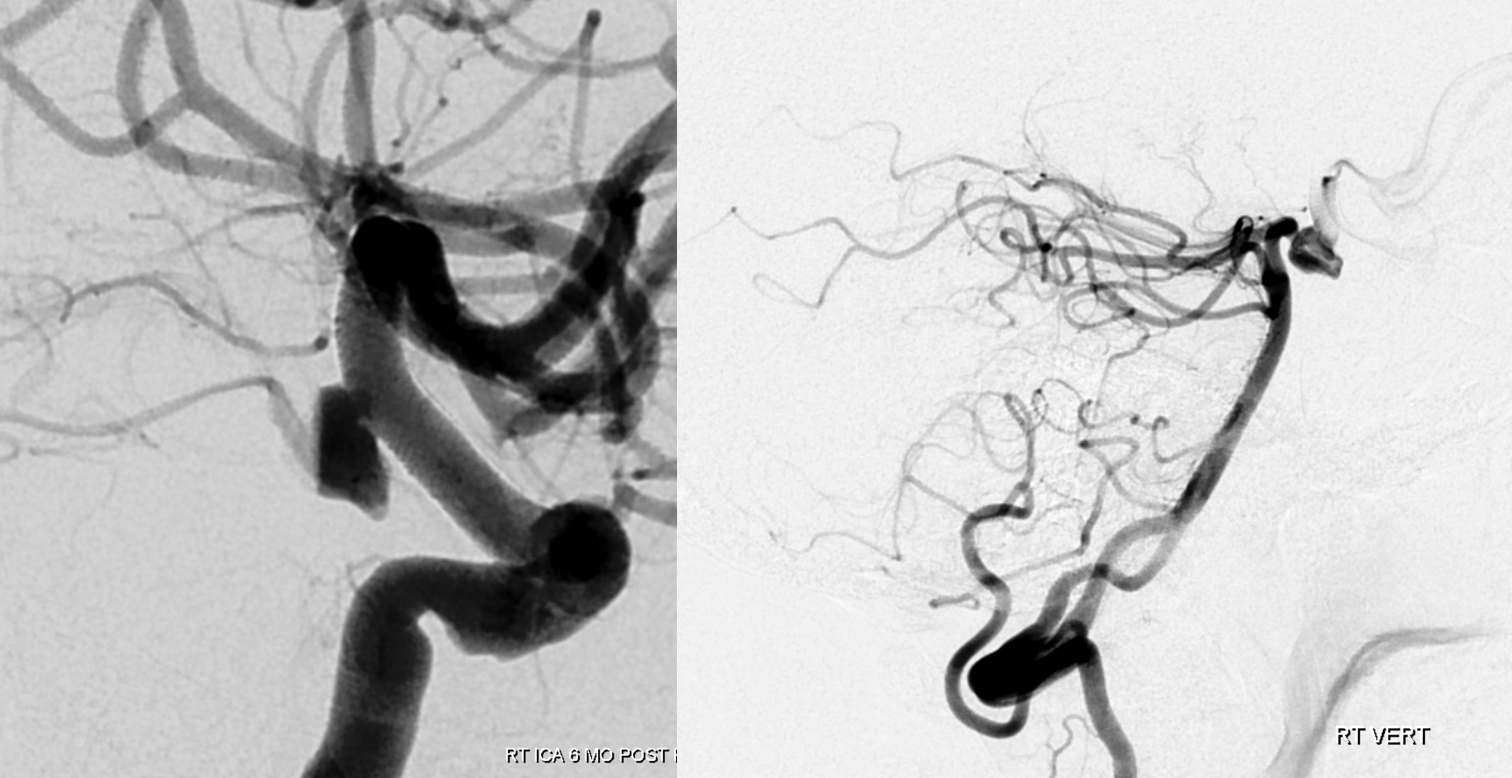

Post 2 PEDs. Typically, with a good P1, this is plenty. Note strategic high coverage over the aneurysm and single choroidal coverage

Two years later — two more pipes are added. Can one argue this is a mistake — if two did not do it, will four? Its a valid point, as you can guess